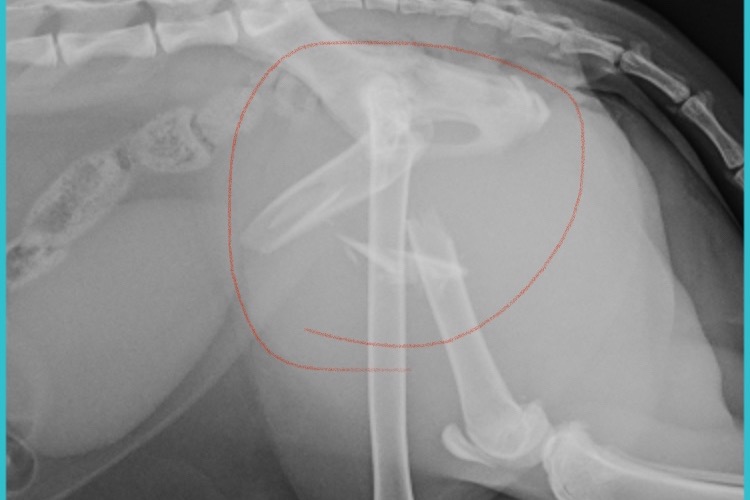

On Saturday night, my dear feline companion Lulu came home with a pained limp. I took her to the vet, who discovered her femur was broken in four places. Lulu had been hit by a car. Her elevated heart rate indicated she was already in agony and would need surgery right away. The vet assured me that Lulu would see a full recovery, but post op treatments, medication and future examinations will put the total cost around $3500. I broke the bad news to my landlord, a senior I share Lulu with. It became apparent that neither of us could afford this emergency expense -- and he regretfully suggested that putting Lulu down was our only option. I couldn't bear the thought; it's just a broken limb and Lulu is more than just a cat. She’s my pal out in the garden, my mouser, and my bodyguard when I leave the house for walks. When I need comfort, she’s right by my side. I couldn't possibly leave hers at this time.